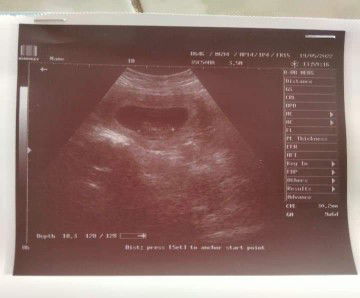

ตอนไม่ท้อง ปกติ น้ำหนัก69-72กก. พอเริ่มรู้ตัวว่าท้อง น้ำหนักจาก69 แพ้ท้องหนัก เหลือ64 ปัจจุบัน อายุครรภ์ 12W+2D (ท้องที่3) อาการแพ้ท้องเบาแล้ว น้ำหนัก 64.4 เริ่มทานอะไรได้มากขึ้นแล้ว พอรู้ว่าท้อง ดื่มนมจืดทุกเช้าและเย็น ทานยาบำรุงทุกวันก่อนนอน มีกังวลมากค่ะ กลัวลูกในท้องไม่สมบูรณ์ไม่แข็งแรง คุณแม่ท่านไหนตั้งท้องน้ำหนักลดเหมือนกันบ้างไหมค่ะ คุณแม่ท่านไหนมีเคล็ดลับดีๆบำรุงลูกน้อยในท้องบ้างไหม ขอคำแนะนำหน่อยค่ะ ขอบคุณค่ะ🙏